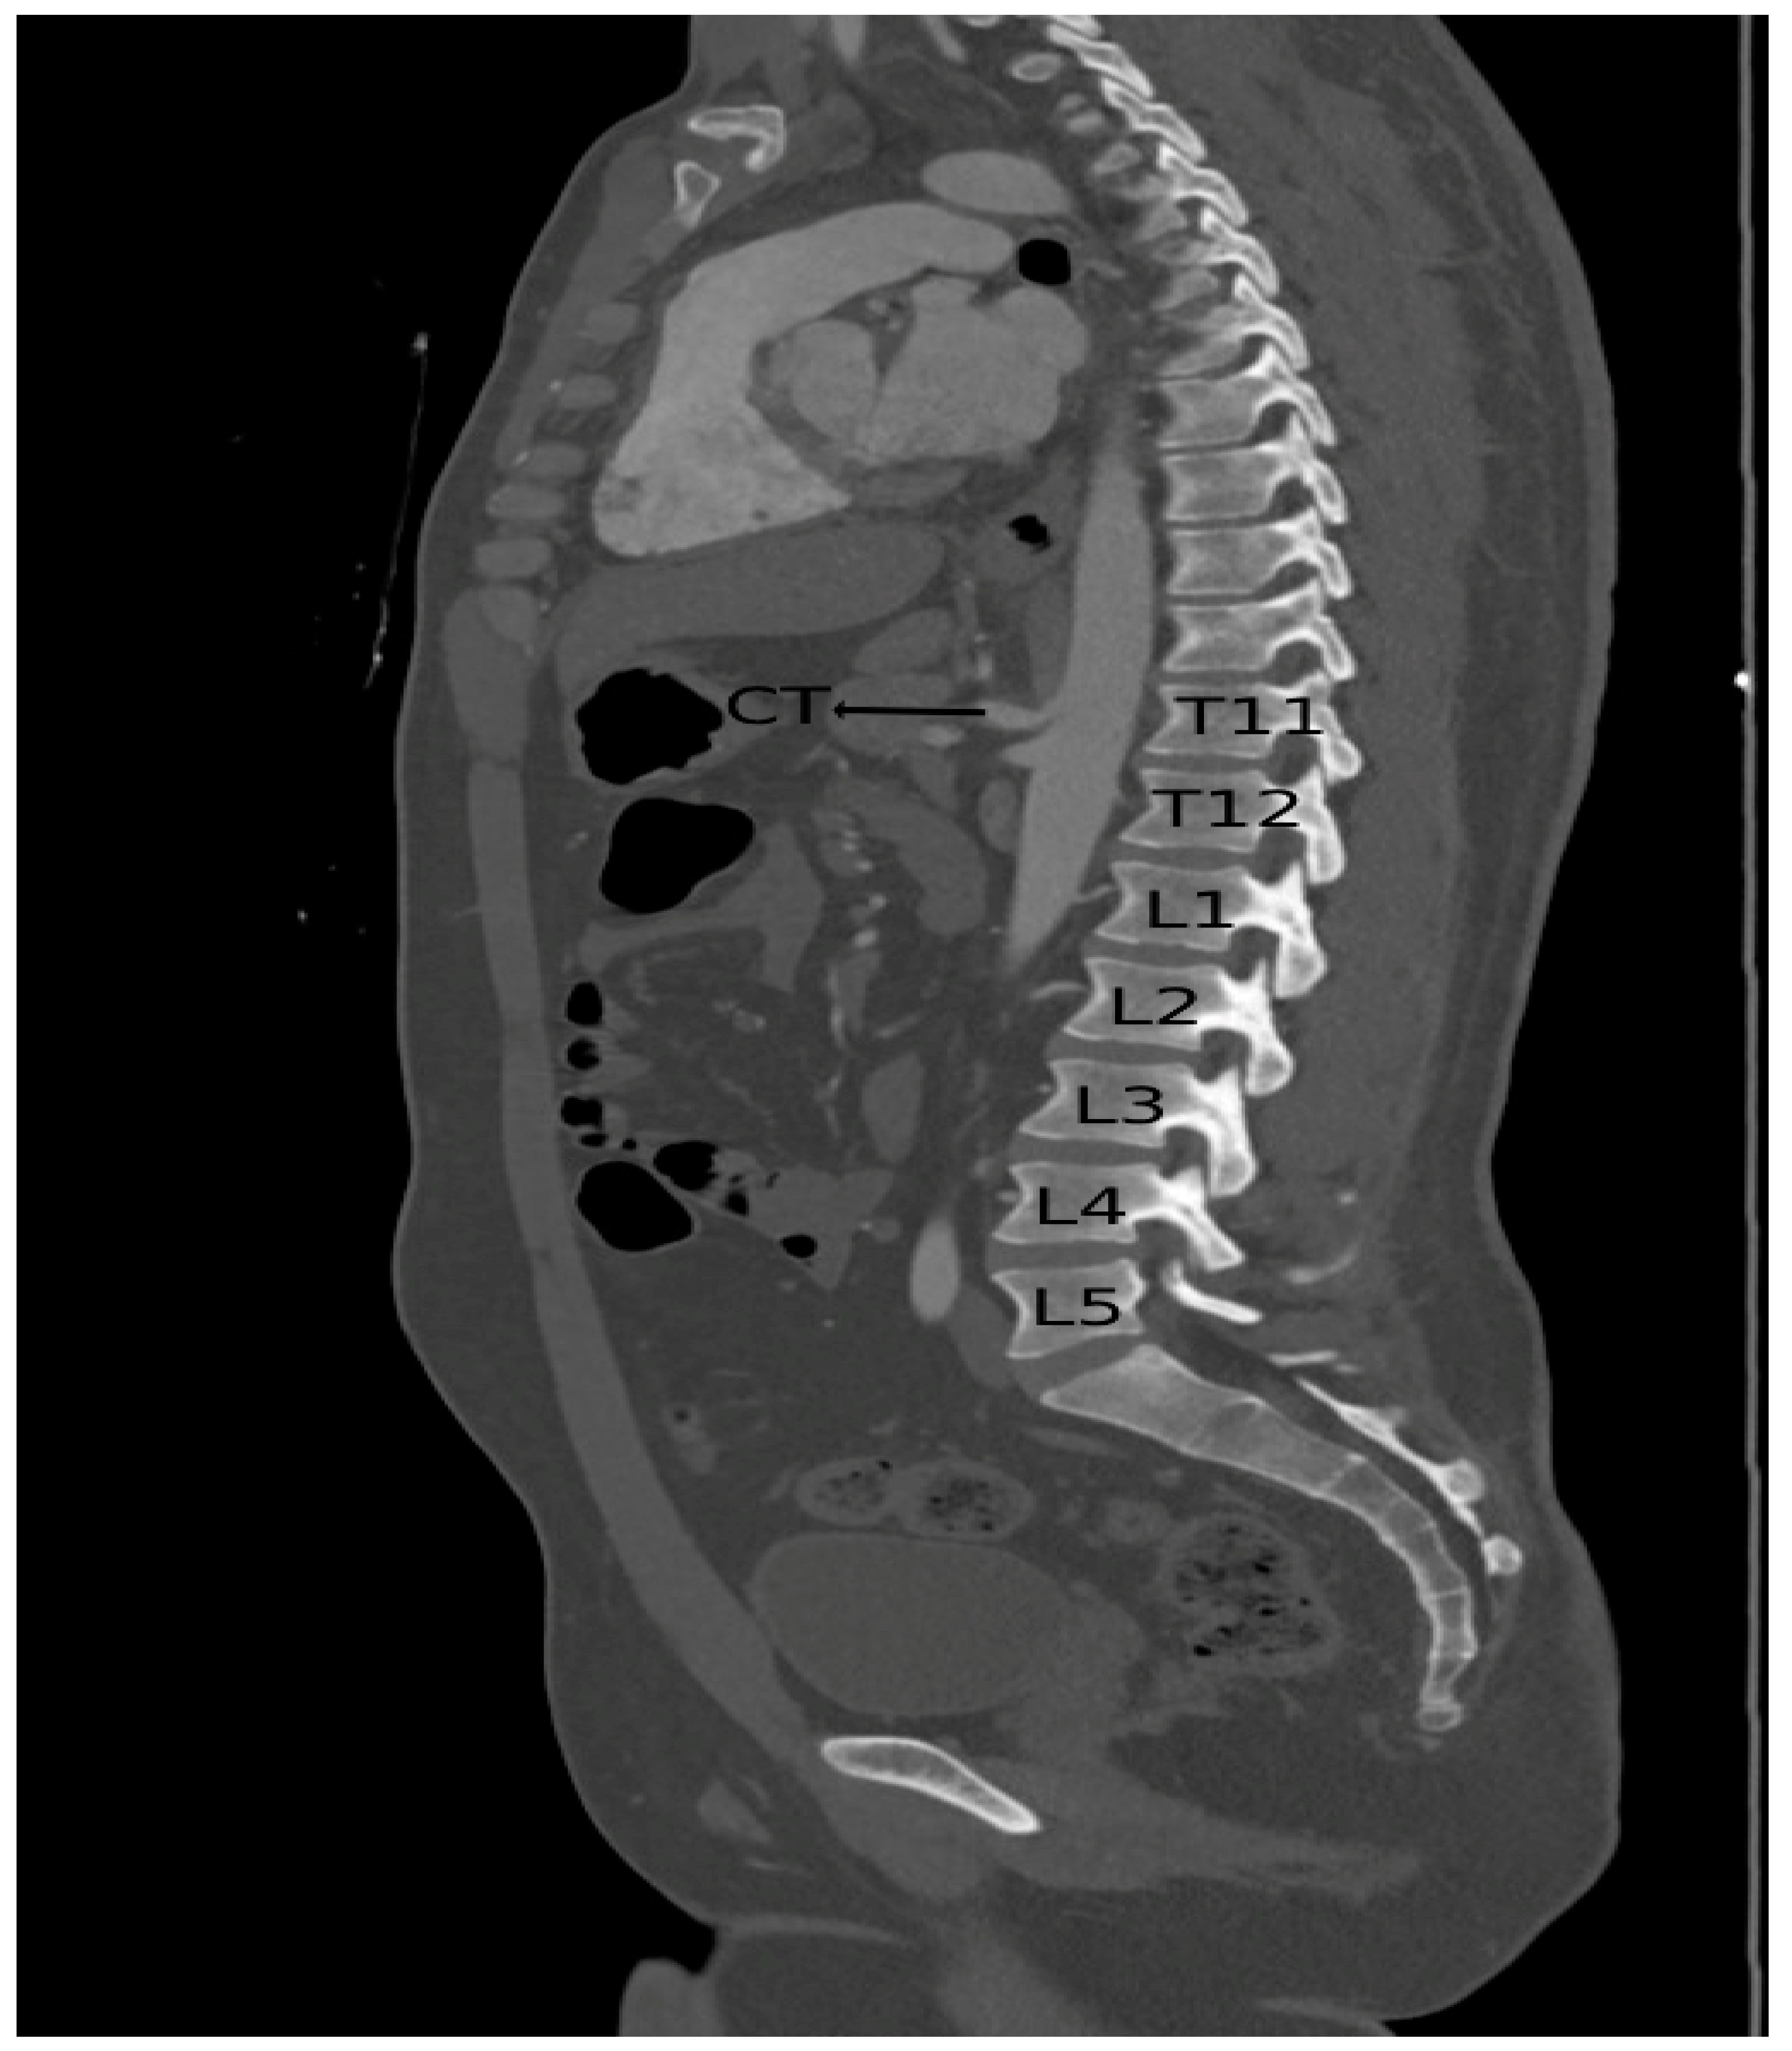

The mean length of the CT in the population of 116 patients (91 males and 25 females) was 20.67 mm (SD = 5.05 mm, range: 11.00–36.00 mm). The mean length in males was 20.75 mm (SD = 4.78 mm, range: 11.00–35.00 mm), while in females, the mean length was 18.51 mm (SD = 5.69 mm, range: 11.00–36.00 mm) and the difference was statistically significant (p value = 0.016). Figure 1 shows the calculation of the length of the CT.

Figure 1. A computed tomography scan shows the calculated length of the CT.

In 85 patients (73.3%), the CT originated at the level of the T12 vertebra. In 25 patients (21.6%), the CT took origin at the level of the L1 vertebra. Figure 3 shows a 3D image of the CT originating at the level of L1. In the other six patients (5.2%), the CT originated from the abdominal aorta at the level of T11. Figure 4 shows the CT originating at the level of T11. The levels at which CT originated in males and females are shown in Table 1.

Figure 4. A computed tomography scan shows CT (celiac trunk) originating at the level of the T11 vertebra in one of the patients.